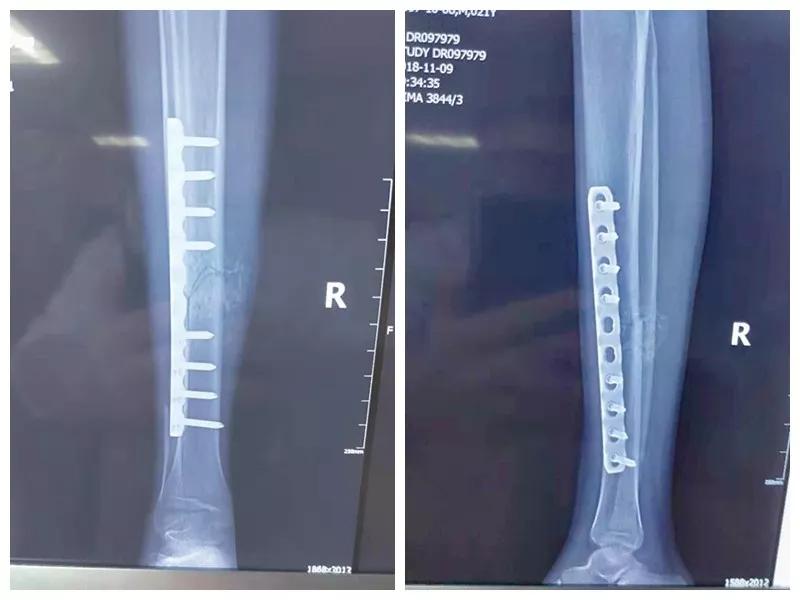

骨二科张延平主任接诊后经仔细询问病史,详细阅读近期X线、CT等病历资料,认为患者骨折移位明显,目前骨折无任何愈合迹象,若保守治疗,骨折将无法愈合,后期不能下地活动,严重影响患者生活质量。同时患者合并慢性再障,血常规结果各项指标均极低,围术期发生麻醉意外、大出血、感染等风险极高;而六合彩生肖作为西安市级最大的三甲综合医院,综合实力深厚,既往相关疾病治疗经验丰富,多次通过多学科诊治为合并复杂内科疾病患者保驾护航,为患者创造手术时机,提高患者生活质量,遂将患者收住院。住院后,立即成立了由张延平主任、杨寅副主任、山卉护士长、梁晨主治医师、刘邦定主治医师、李鑫护师组成的手术治疗小组。经初步检查,患者血常规结果较当地检验结果更差,三系细胞均极低,其中血小板仅为1(正常值为100-300),血红蛋白55g/L。遂立即请血研所李罡灿主任医师会诊,给予升高白细胞、纠正贫血、升高血小板等治疗,经积极治疗患者血常规各项指标均较入院时改善。张延平主任再次组织由血研所李罡灿主任医师、麻醉科崔晓岗主任、感染科付建军主任、药剂科韩小年副主任药师等参加的术前讨论。讨论后一致认为患者目前各项指标虽然较入院时改善,但因其慢性再障病史长,骨髓造血及储备能力极差,围术期发生大出血、伤口感染甚至全身感染等风险仍极高,术中及术后需准备大量血小板防止大出血,同时需高度警惕手术切口、取骨区术后发生感染。为尽快为患者施行手术,治疗小组积极联系输血科为患者备血,并为患者制定了围术期抗感染方案;在六合彩生肖输血科存血量严重不足的状态时,输血科张养民主任亲自联系市中心血站为患者准备手术中及术后所需的血小板制品。手术小组为患者制定了周密的手术方案及风险预案,10月31日,在麻醉科王永宏副主任医师、手术室高洁、赵耀护师的配合下,为患者施行了右胫骨粉碎性骨折切开复位、髂骨取骨植骨内固定术,手术历时70分钟,安全返回病房。术后患者渗血多,1周内连续每日平均渗血超过100ml,并出现发烧,最高39℃,复查血常规三系细胞较术前再次明显降低。李罡灿主任医师、付建军主任、韩小年副主任药师多次来科会诊,及时调整患者的治疗方案,输血科再次为患者的救治提供了强有力的支援和保障。在山卉护士长带领的护理团队精心护理下,患者未发生压疮等卧床并发症。目前该患者术后恢复良好,已出院进行下一步康复治疗。